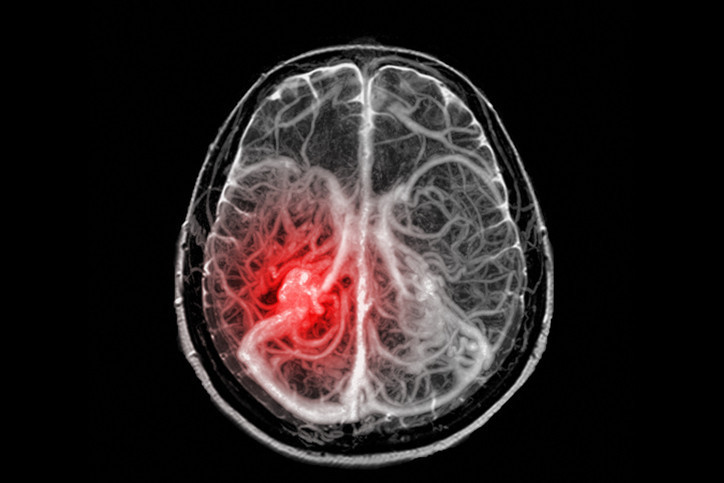

Hastanede triyaj odasına alınan ve kusmaya başlayan Moroney için dönüm noktası, annesinin tarama yapılması konusundaki sert ısrarı oldu. Yapılan BT taraması sonucunda beyninde bir tümör olduğu tespit edildi.

Daha sonra Cambridge’deki Addenbrooke’s Hastanesi’ne sevk edilen genç kıza burada acı haber verildi: Eğer tümör hemen alınmazsa bir ay içinde hayatını kaybedecekti. 17 Şubat’ta gerçekleşen başarılı bir operasyonla tümörün büyük bir kısmı temizlendi.

Ameliyat sonrası yapılan biyopsi, durumun tahmin edilenden daha karmaşık olduğunu ortaya koydu. Moroney’ye, genellikle 5 yaş altı çocuklarda görülen ve yetişkinlerde rastlanması son derece nadir olan 4. Evre Atipik Teratoid/Rhabdoid Tümör (AT/RT) teşhisi konuldu.